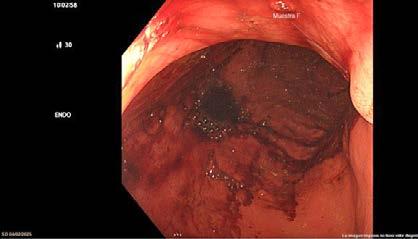

El día 18/2/2022 el paciente refiere dolor torácico. Se realiza un electrocardiograma, que muestra elevación del segmento ST en las derivaciones anteriores en relación con un infarto agudo de miocardio (IAM) anterior. Se activa código infarto y se realiza una coronariografía emergente, que muestra una oclusión de perfil embólico en la arteria descendente anterior media (Figura 1, flecha amarilla). Se trata con trombectomía aspirativa con buen resultado angiográfico final con flujo TIMI 3. Se inicia tratamiento con perfusión de heparina sódica. El día 19/2 el paciente comienza con cefalea muy intensa y afasia, por lo que se activa nuevamente código ictus y se realiza un angioTAC craneal que muestra una hemorragia subaracnoidea (HSA) de predominio izquierdo secundaria a sangrado por un aneurisma disecante de la rama M2 de la arteria cerebral media izquierda (Figura 2, flecha amarilla). Se decide completar estudio con una angiografía que confirma los hallazgos del TAC. Por el alto riesgo de resangrado y la necesidad de anticoagulación oral permanente, se decide embolización del aneurisma con coils, que resulta exitoso (Figura 3, flecha amarilla). Se reinicia durante el ingreso perfusión de heparina sódica y unos días antes del alta se comienza con anticoagulación oral con apixaban 5 mg/12 horas. La evolución clínica es favorable, siendo la exploración física al alta normal. Tras tres años de seguimiento bajo tratamiento con apixaban 5 mg/12 horas no han sido reportados nuevos episodios de sangrado ni de trombosis.

Se realizó una tomografía computarizada (TC) con contraste de forma emergente, que mostró una disección aórtica iatrogénica tipo A focal de origen en la zona 0 del cayado con extensión al tronco braquiocefálico derecho (1) sin afectar al resto de troncos supra-aórticos, cayado o aorta descendente (Figuras 1 y 2); además del hematoma

Figuras 1 y 2: Prótesis aórtica migrada y disección aórtica focal tipo A, de origen en la curvatura menor del arco aórtico (zona 0) hasta la bifurcación de la arteria braquiocefálica derecha; sin afectación de del resto de troncos supra-aórticos, del resto del cayado aórtico o de la aorta descendente.